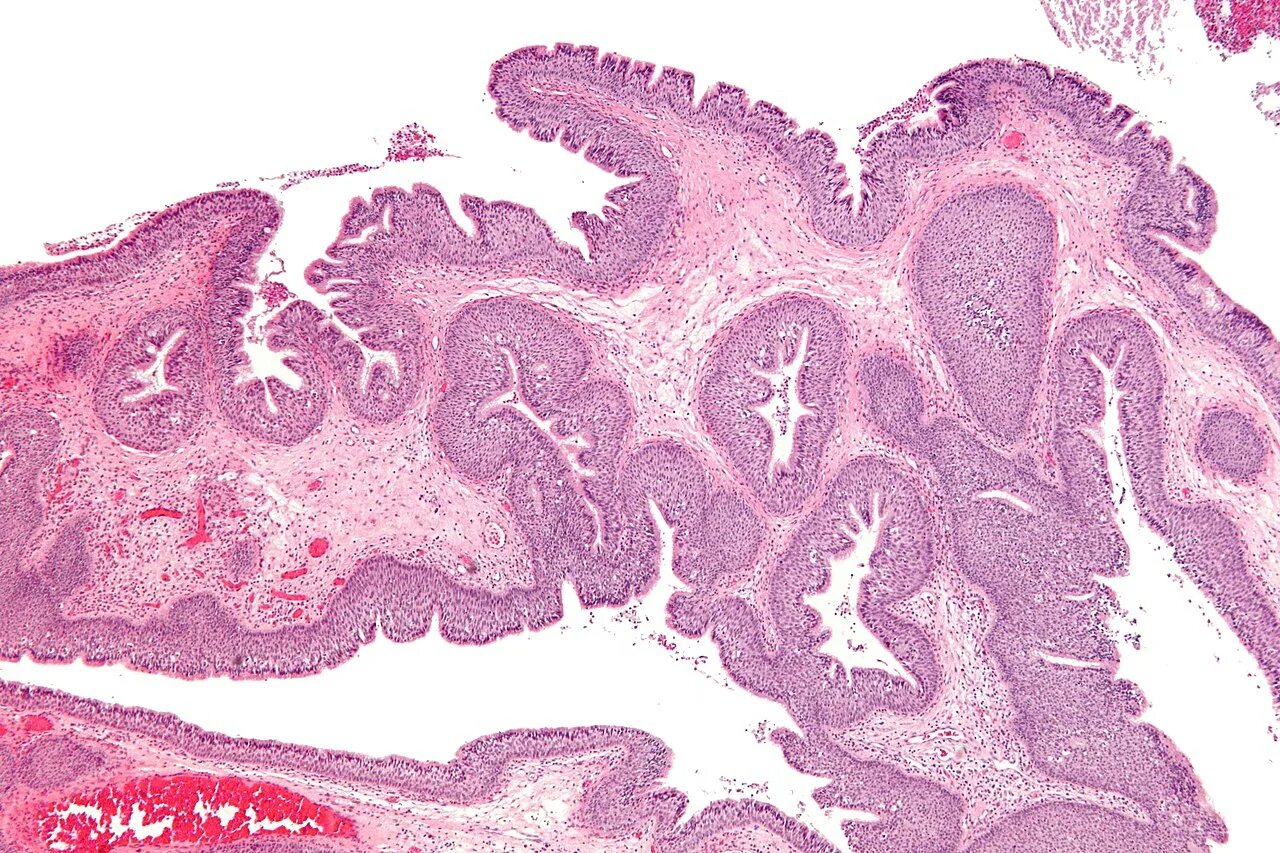

Гистология слизистой